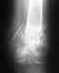

Здравствуйте! Возможно ли исправить то что неправильно срослось? Или мне грозит всё-таки инвалидность? Снимки прилагаю.

Получила травму 20.11.11 внутрисуставной оскольчатый перелом дистального конца обеих костей левой голени, после месяца на вытяжке поставили аппарат илизарова, через 4мес сняли, нога кривая, даже приступить не могу, резкая боль. Что Вы мне можете рекомендовать?

• Кликните для загрузки файла SSCN0279.jpg